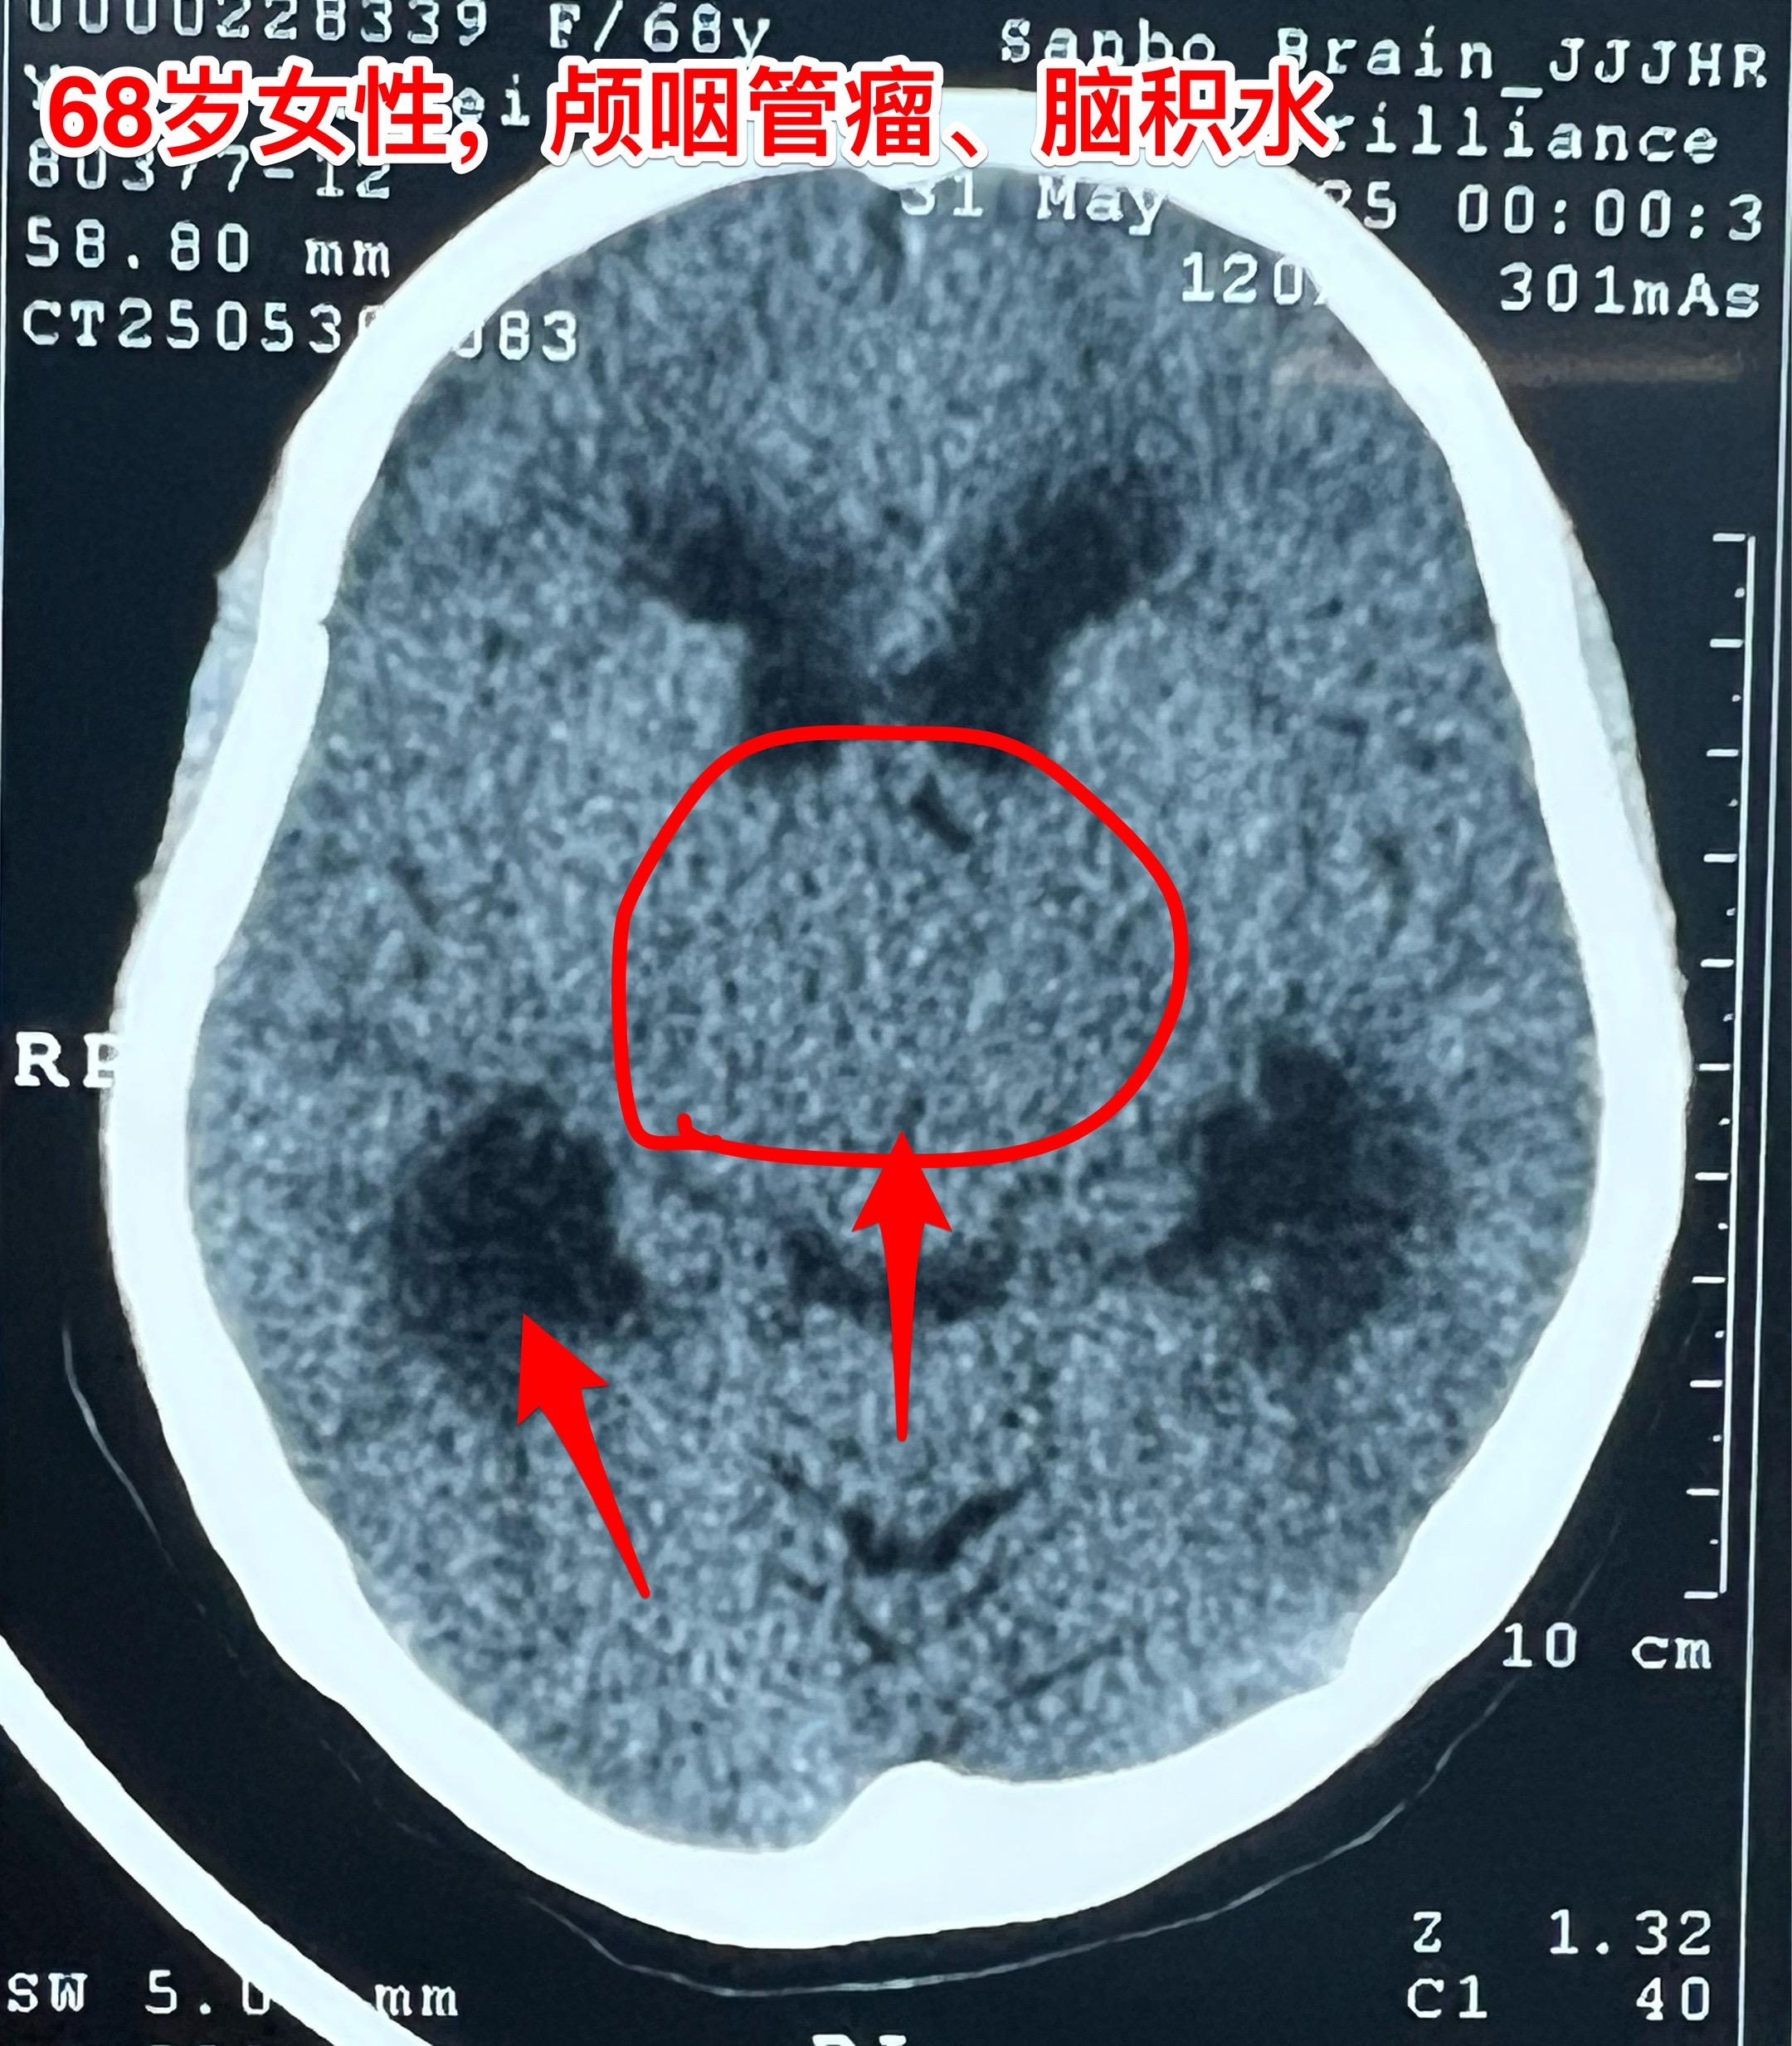

68岁老人患颅咽管瘤是否可以作手术? 颅咽管瘤并非小孩子的病,老年人也可以患颅咽管瘤。 过去十年间我科治疗过颅咽管瘤患者共计1153例次,其中53例患者年龄在60-74岁。 所以,老年人患颅咽管瘤也不是手术禁忌。 这个68岁南通市女病人因颅咽管瘤造成视力下降、头晕症状,住院前一天出现反复呕吐症状,提示颅内压升高,所以应该尽早作手术,否则会造成生命危险。2025年6月8日作了开颅手术,颅咽管瘤得到完全切除。幸运的是垂体柄受肿瘤侵蚀的不严重,得以保留。今天是手术后第